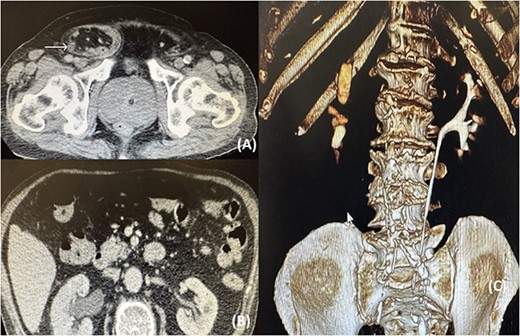

A computed tomography (CT) was ordered that revealed a significant pelvicalyceal dilatation and hydronephrosis of the right kidney consistent with obstructive uropathy and a medium-sized right inguinal hernia containing fat, bowel loops, and the right ureter (Fig. 1).

(A) CT image showing the right ureter (arrow) entrapped within the hernia; (B) CT image showing the pelvicalyceal dilatation of the right kidney because of the distal ureteral entrapment; (C) CT reconstruction showing no illustration of the right ureteral system.